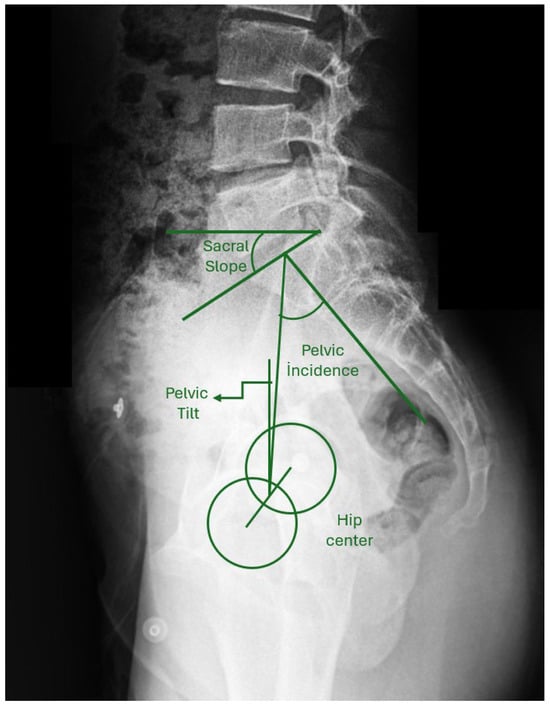

Background/Objective: The anterior vertebral body tethering (AVBT) technique, which preserves spinal mobility and avoids possible fusion problems in adolescent idiopathic scoliosis (AIS) patients, continues to be increasingly used in spine surgery. The study aims to report the early-to-early-mid postoperative radiological results of thoracolumbar/lumbar AVBT on sagittal alignment, and the second aim is to compare AVBT with selective thoracic fusion (STF) and non-selective fusion (NSF) groups in AIS patients. Methods: Patients with a diagnosis of AIS were retrospectively evaluated in the study. All patients were categorized into three groups based on the surgical technique performed: AVBT (n = 17), NSF (n = 19), and STF (n = 15). The major curvature degree, coracoid height difference (CHD), sacral slope (SS), pelvic tilt (PT), pelvic incidence (PI), lumbar lordosis (LL), thoracic kyphosis (TK), cervical lordosis (CL), C7 tilt, sagittal vertical axis (SVA), T1 pelvic angle (TPA), and T1 spinopelvic inclination (T1SPI) were measured for radiological comparison. Scoliosis Research Society-22 (SRS-22) and Oswestry Disability Index (ODI) scores were used at the final follow-up for functional evaluation. Results: The T1SPI value of the NSF group was significantly higher than the STF group in the final follow-up (p = 0.033). The mean decrease of 8.85 ± 7.85 units in the final follow-up value compared to the postoperative CHD value of the patients in the AVBT group was found to be significant (p = 0.028). Statistically significant differences were found between preoperative and the first postoperative CL and TPA measurements (p = 0.001 and p = 0.042, respectively), as well as between preoperative and final follow-up CL measurements in the AVBT group (p = 0.001). No statistically significant differences were observed between the groups in CHD, SS, PT, PI, LL, TK, CL, C7 tilt, SVA, and TPA values (p > 0.05); similarly, the SRS-22 and ODI scores did not differ significantly among the groups (p > 0.05). Conclusions: Thoracolumbar/lumbar AVBT surgery led to significant improvements in shoulder asymmetry and cervical lordosis of AIS patients in the early to early-mid postoperative period. However, compared with spinal fusion techniques, thoracolumbar/lumbar AVBT did not demonstrate superiority in functional scores or sagittal parameters. The mid- to long-term benefits of thoracolumbar/lumbar AVBT remain uncertain and require further investigation. Full article

Figure 1